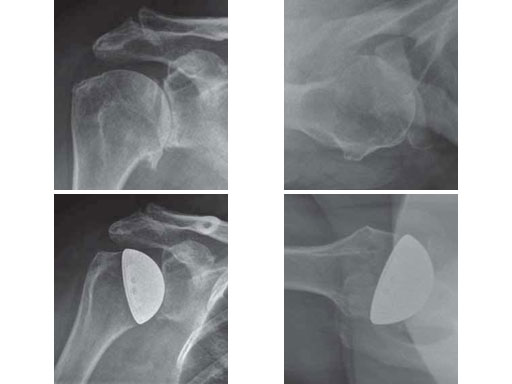

67-year-old female with a primary omarthrosis on the right side.

Case provided by Norbert P Sdkamp, Martin Jaeger, Freiburg, DE, Ralph Hertel, Bern, CH

Fig 4ab Fracture situation in conventional x-rays.

Fig 4cd Implantation of a resurfacing head type EPOCA.